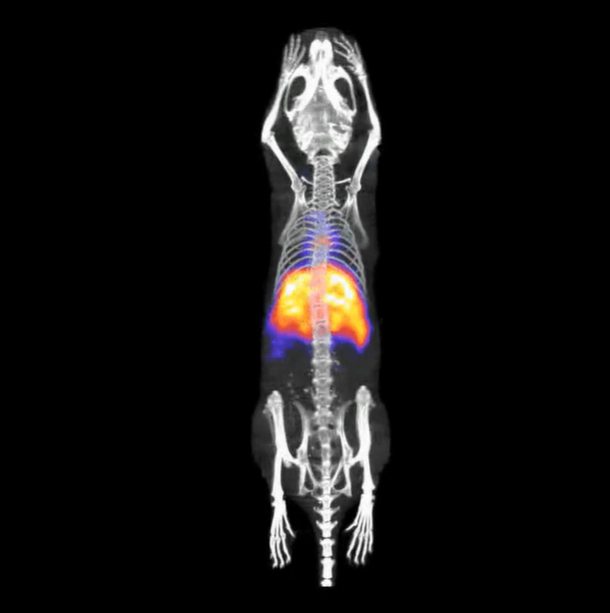

对三只小鼠进行同步成像观测

较大的单床位视野范围以及较高的灵敏度使得可以对三只小鼠同时进行成像检测,从而显著提升检测效率,实现前所未有的检测速度。

〉实验对象:3只体重为20克的小鼠

〉放射性示踪剂:99mTc-锝酸盐,其放射性活度为16.6至18.7 MBq(相当于450至500 µCi)。

〉准直器:采用高灵敏度、高分辨率的多孔结构,专为对大鼠进行全身成像检测而设计。

〉数据采集方式:采用螺旋形SPECT扫描方式来进行数据采集。